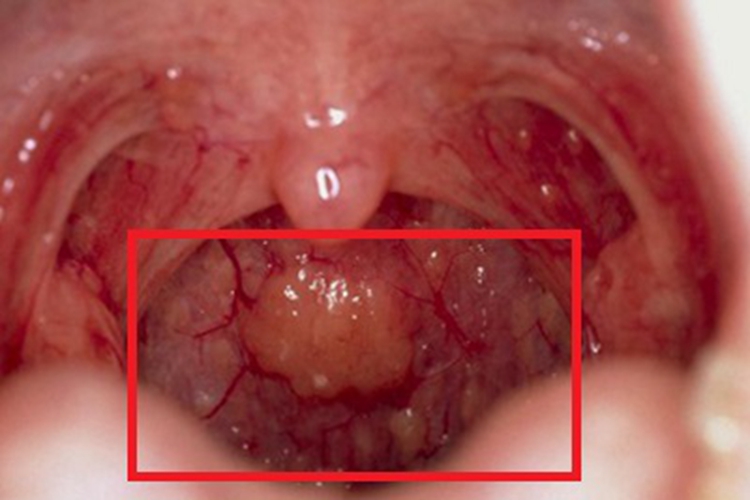

慢性咽炎可导致咽喉红肿,同时咽后壁有淋巴滤泡增生融合成的包块。

慢性咽炎可导致咽喉黏膜出现不同程度的充血、红肿,同时血管扩张,咽后壁有散在淋巴滤泡增生,可为散在分布,也可融合呈包块,常有少量黏稠分泌物附着在黏膜表面,患者可出现咽部异物感、痒感、干燥感等不适。